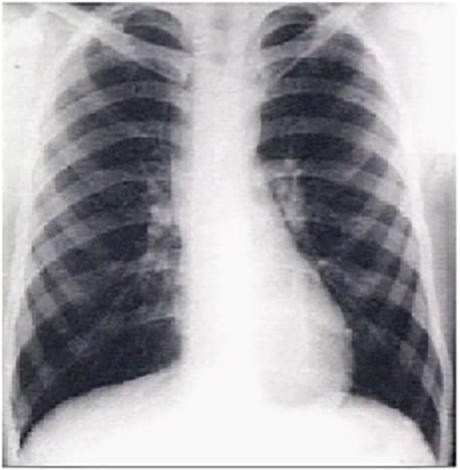

Dilated Ascending Aorta (PA and lateral)

These chest X rays show a dilated ascending aorta.

The PA view demonstrates dilatation of the ascending portion of the aorta as evidenced by a prominent bulge in the right mediastinal shadow. Note that the heart size is normal, as reflected by a cardiothoracic ratio less than 50%. The lateral view shows a dilated ascending aorta as evidenced by the shadow anterosuperior to the heart.